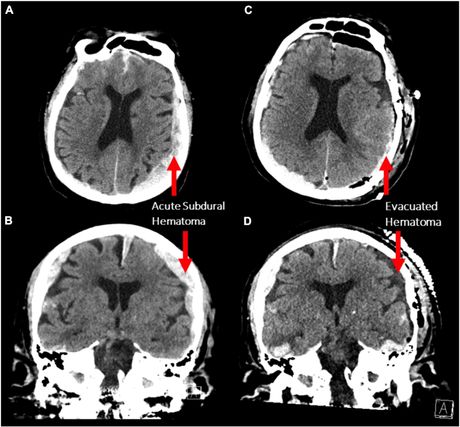

Pacijent (87) se lečio od epilepsije i bio je priključen na EEG. Merena mu je moždana aktivnost kada je iznenada doživeo srčani udar i preminuo. Ostalo je zabeleženo petnaestak minuta, računajući i trenutak kada je pacijent izdahnuo.